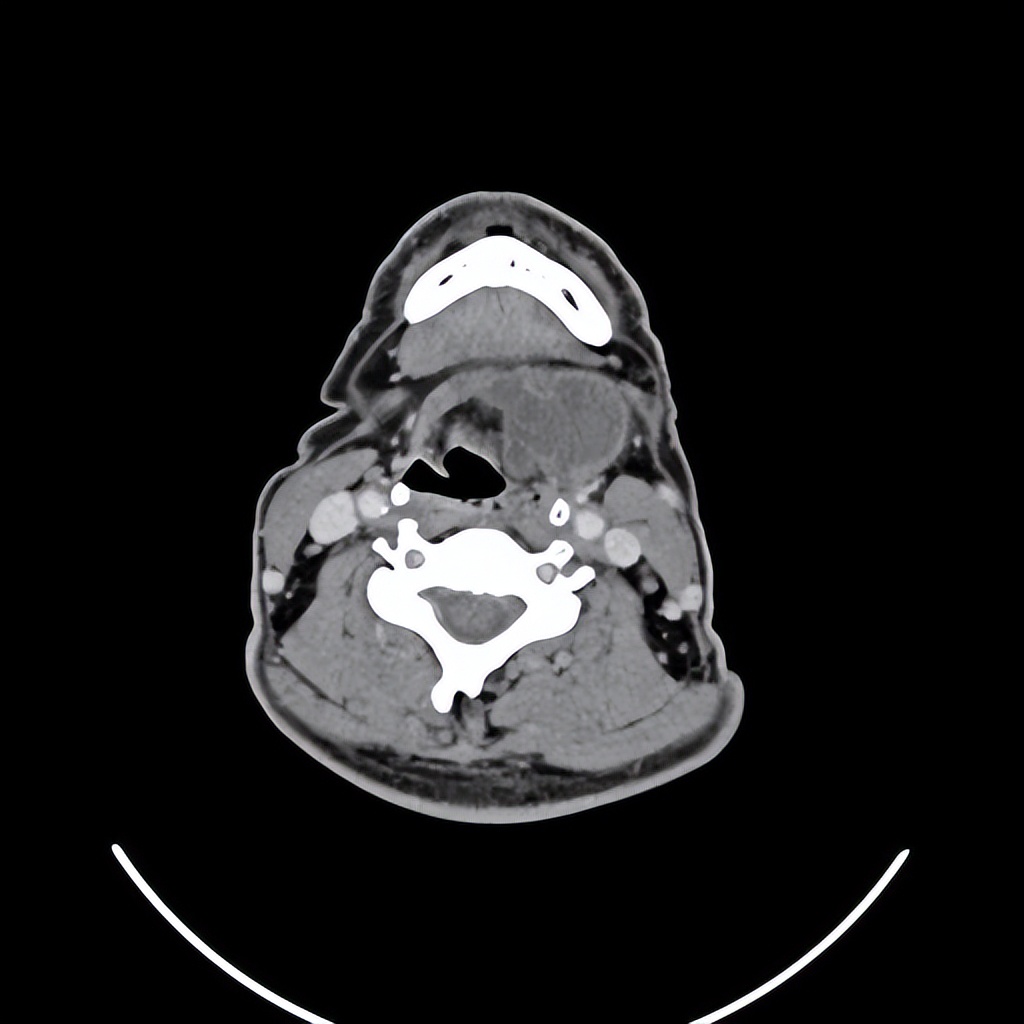

来自广东梅州的管叔,最近发现颈部肿物2周,不痒,不痛,自觉问题不大。但是肿物越来越大了,在家人的劝说下来到佛山复星禅诚医院耳鼻喉做了检查发现是颈部的先天性囊肿。

这个年龄阶段发现颈部的先天性囊肿是比较少见的,一般这种病没有多少的不舒服,但需要做手术切除才可以根治。一般手术早点做效果要好一些,如果囊肿长的比较大了,手术的范围也会相应的扩大,术后恢复就可能会慢一些,手术的风险也会相应的增大。